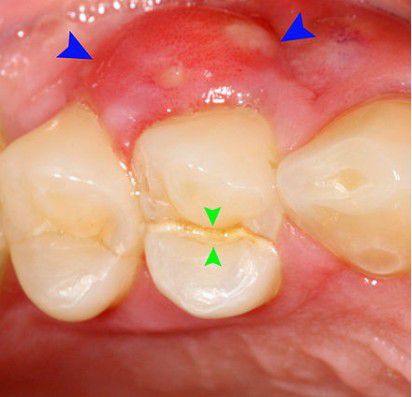

Cracked tooth syndrome

Crack (vertical fracture) of tooth and root (green arrows) splitting it in two even pieces which has caused a lateral periodontal abscess (blue arrows).